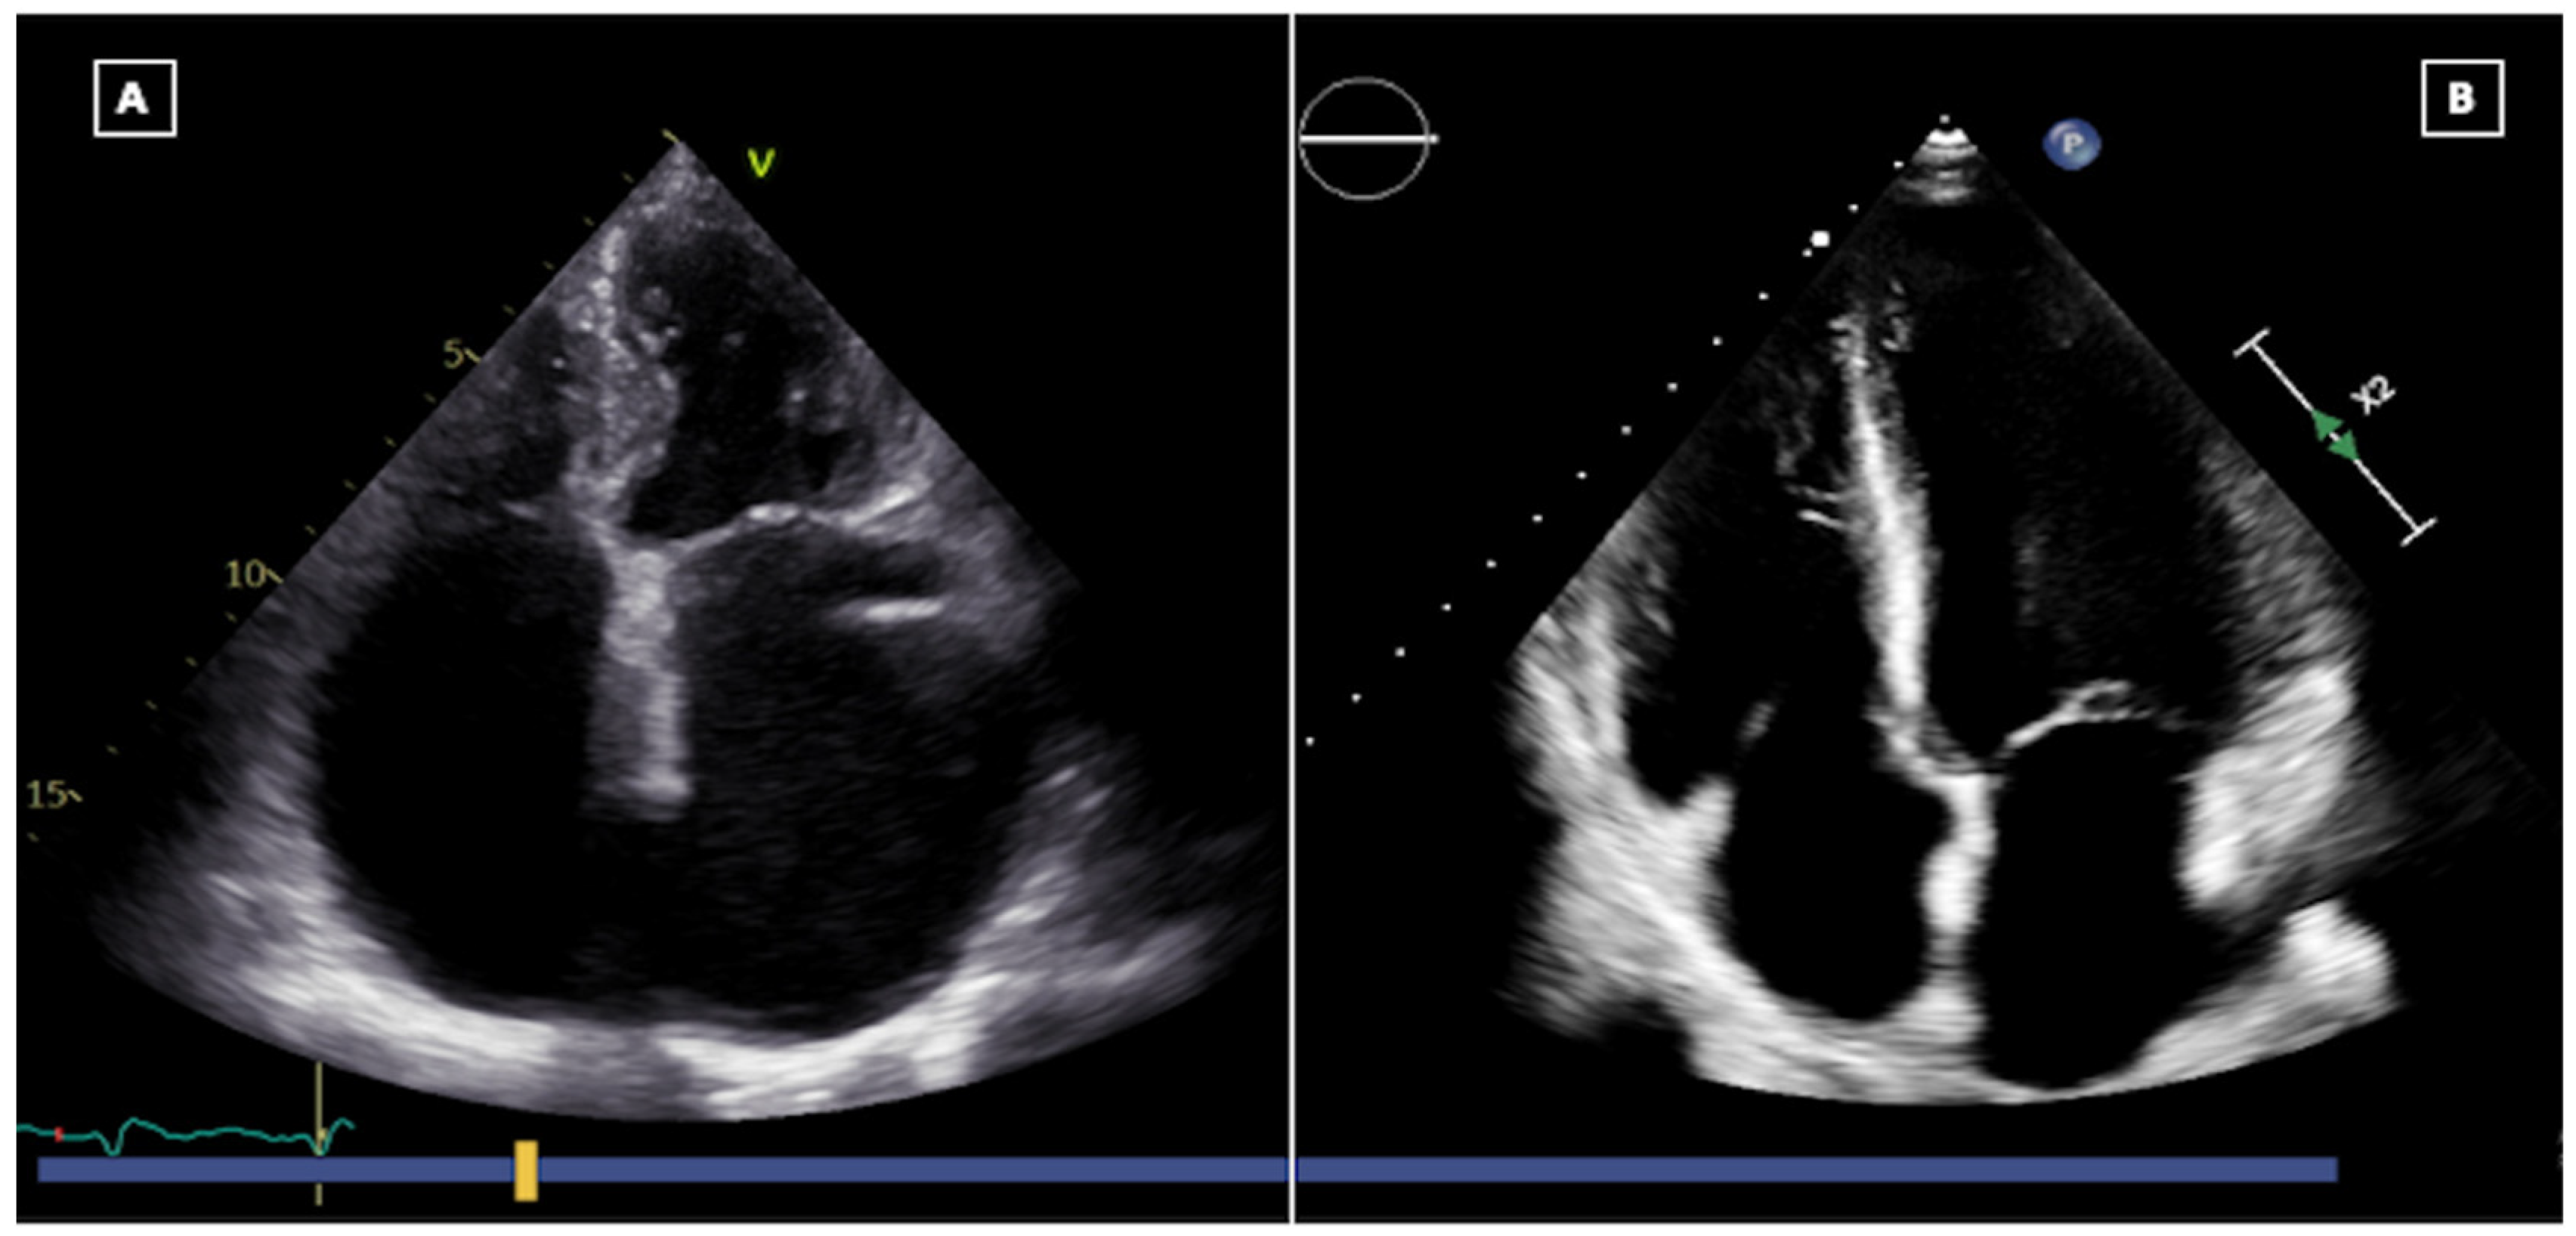

2. Echocardiography of the Normal Cardiac Allograft

2.1. Evaluation of Left Ventricular Function

2.2. Evaluation of Right Ventricular Function

2.3. Evaluation of Postoperative Valvular Function